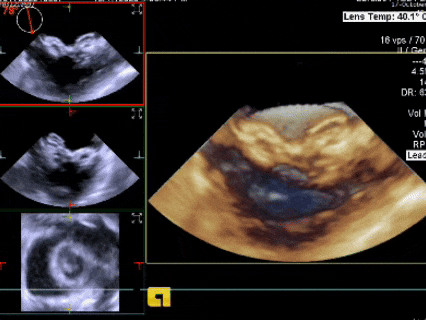

三维下可见房间隔缺损

三维下看到导丝成功过隔